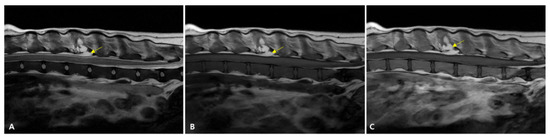

2. Case Description